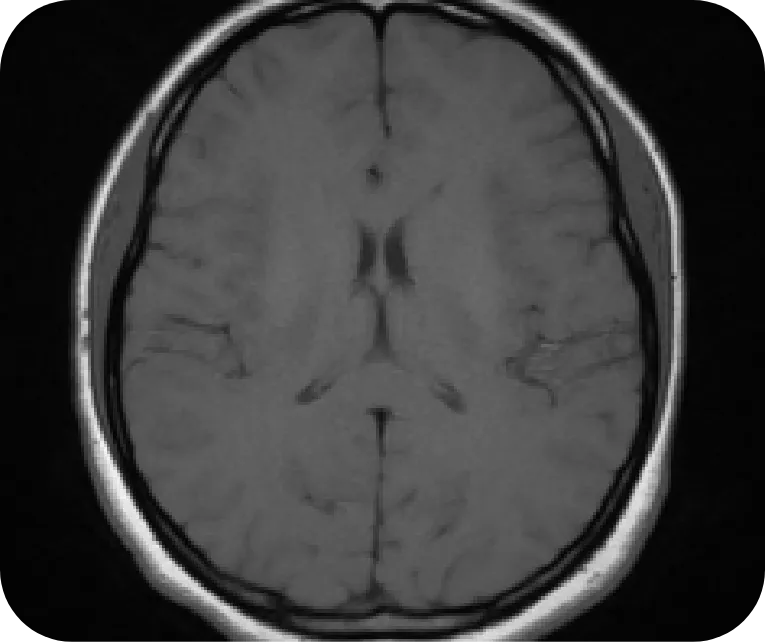

Brain

Normal

Axial T1-weighted image of a normal brain

Courtesy of Associate Professor Frank Gaillard, Radiopaedia.org, rID:37605.